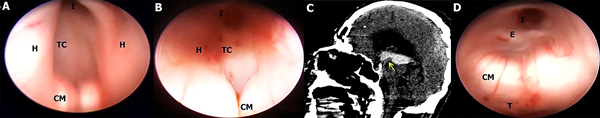

En este estudio fueron halladas 10 variedades anatómicas del piso anterior del tercer ventrículo, las cuales son en orden de frecuencia: piso opaco o grueso 54,90% (Figura 1), piso parcialmente borrado 29,41% (Figura 2), intervalo prepontino pequeño 23,53% (Figura 3), piso estrecho 17,65% (Figura 4 A-B), piso herniado 17,65% (Figura 5), piso delgado 11,76% (Figura 6), basilar elevando el piso 1,96% (Figura 4C-D), adherencias interhipotalámicas 3,92% (Figura 7), fenestración espontánea 1,96% (Figura 8), y piso sin reparos anatómicos 1,96% (Figura 9). Las primeras 7 según la descripción de Sughrue, a la cual se sustituye banda premamilar por adherencias interhipotalámicas, descriptas por Phillips4, fenestración espontánea al hallarse ausencia de PTV u ostomía espontánea como en la Fig. 8, reportada por Parmar5, y se introduce otra categoría no reportada, piso sin reparos anatómicos cuando no se pueden diferenciar los cuerpos mamilares ni el receso infundibular. En la mayoría de los casos se detectaron 2 o más variedades.

Figura 6: A; Hombre con hidrocefalia crónica del adulto. El piso es traslúcido y los CM y el complejo basilar se pueden visualizar con facilidad, disminuyendo el riesgo de injuria vascular. Cuerpos mamilares de tipo Split, separados. B; Otro caso de hidrocefalia crónica del adulto con falla de TVE que se reinterviene endoscópicamente, donde se evidencia ostoma pequeño en TC, el cual es tan delgado que permite ver la arteria basilar y sus ramas ampliamente, con CM separados. C-D Mujer con hidrocefalia congénita, con disfunción de DVP, con un piso notoriamente delgado a través del cual se identifican todas las estructuras de la cisterna interpeduncular y prepontina, incluido todo el recorrido de la AB y cerebrales posteriores, el tercer par craneal izquierdo y el puente.

AB arteria basilar; AP arterias perforantes; CM cuerpo mamilar; CP Cerebral posterior; D dorso selar; H hipotálamo; I Receso infundibular; Os ostoma; Q quiasma óptico; P puente; T tegmentum mesencefálico; TC Tuber cinereum.

En cuanto al tiempo de clínica de hidrocefalia, hubo 32 casos de hidrocefalia aguda (HA) y 19 casos de hidrocefalia crónica (HC). Se determinó, a su vez, en la forma de presentación aguda una mayor frecuencia de piso opaco (n 23/32, 71,8%) y de piso estrecho (n 8/32, 25%). En tanto que en los casos de HC predominó la presencia de piso delgado (n 6/19, 31,58%), el cual se observó exclusivamente en esta categoría, con 0 casos en hidrocefalia aguda. El resto de las variedades de piso se halló en una frecuencia similar en la hidrocefalia aguda y crónica. La asociación del piso opaco con el tiempo de clínica de hidrocefalia fue estadísticamente significativa, con un odds ratio de 7,15 (p 0,001469). Es decir que se observó una frecuencia de piso grueso 7 veces mayor en los pacientes con hidrocefalia aguda en comparación con los que exhibían una hidrocefalia crónica.

Las variaciones observadas con mayor frecuencia están en el grosor del piso y en su posición. En los casos de dilatación ventricular aguda, por ejemplo, en la hidrocefalia inducida por tumores de fosa posterior (Figura 7 A-B) o por disfunción valvular (Figura 1 C-D), e hidrocefalia postinflamatoria (figura 3C) el PTV puede estar sin distensión y extremadamente grueso, sin ningún tipo de transparencia y con los cuerpos mamilares difícilmente reconocibles. Por el contrario, en los casos de ventriculomegalia de larga data debido a hidrocefalia crónica, como los que se puede observar en algunos pacientes con estenosis acueductal, el PTV puede estar extremadamente distendido y protruir hacia la cisterna interpeduncular debido al gradiente de presión entre el tercer ventrículo y el espacio subaracnoideo, y ser delgado y transparente.3,6,7 Esto es consistente con la teoría que dice “el grado de hidrocefalia es inversamente proporcional al grosor del PTV”. Un piso delgado significa que la perforación puede lograrse sin mucha fuerza o manipulación, reduciendo el riesgo de lesión del complejo basilar y del hipotálamo.3 A pesar de esto, un piso grueso se puede presentar también en hidrocefalia crónica. Rohde2 reportó una incidencia de 16% de piso grueso y Iaccarino8 de 48%. Un piso engrosado se ha asociado con aumentos en el tiempo quirúrgico, contusiones e incidencia de diabetes insípida debido a una manipulación quirúrgica y estiramiento más enérgicos del hipotálamo. El riesgo de daño a la arteria basilar y las arterias pequeñas del tuber cinereum también aumentaría, aunque no existen cifras oficiales que apoyen esto.3

Laccarino8 y col. revisaron los videos y estudios prequirúrgicos de 23 pacientes con hidrocefalia y las RM de cerebro de 120 voluntarios control sanos para determinar la distancia intermamilar (DIM) normal. Hallaron la presencia de dos variedades en la RM; configuración “kissing”, en beso o unidos, donde no hay distancia medible entre los cuerpos mamilares, siendo la más frecuente entre los sanos, y la configuración “split” o separados, donde hay distancia intermamilar medible. A su vez, observaron que en la visión endoscópica los cuerpos mamilares físicamente separados se correspondían con una DIM mayor a 2 mm en la RM preoperatoria, y que cuando no se hallaba distancia entre los cuerpos mamilares endoscópicamente, una mínima DIM (menor a 2 mm) podía estar presente en la RM. Ellos encontraron una asociación entre el incremento en la DIM con el grosor del PTV. Concluyeron que la configuración normal de cuerpos mamilares es la kissing, con un leve Split en pacientes con atrofia cerebral relacionada a la edad; y en pacientes con hidrocefalia, un PTV grueso fue hallado casi exclusivamente en los casos con un incremento en la DIM en la RM y con cuerpos mamilares separados en la visión endoscópica.8 En contraste, Sughrue3 describe en su serie de casos que 4 de 5 pacientes con PTV grueso presentaron cuerpos mamilares adyacentes y que 4 de 4 pacientes con piso Delgado tenían cuerpos mamilares separados en la visión endoscópica, asemejándose a nuestros hallazgos.

Las variantes endoscópicas del PTV son frecuentes y se relacionan con el tiempo de hidrocefalia de forma significativa. La identificación de la arteria basilar a través de un piso delgado o parcialmente borrado, y un PTV de amplias dimensiones (no estrecho) favorecen una adecuada y sencilla fenestración del piso ventricular, hallándose estas características principalmente en casos de hidrocefalia crónica. En cambio, en la hidrocefalia aguda, como la provocada por una hemorragia intraventricular, predomina un piso de tipo grueso y estrecho, que dificulta la TVE pero no impide su ejecución. Saber esta incidencia permite al neurocirujano predecir la presencia de un piso opaco a través del conocimiento de la evolución clínica de la patología. A su vez, según los datos obtenidos, la disposición kissing de los cuerpos mamilares se encuentra vinculada con mayor frecuencia con la presencia de un piso grueso, y esta configuración se puede evaluar en la RM cerebral (Iaccarino8), por lo que se podría predecir el grosor del PTV prequirúrgicamente tanto a través de la epidemiología como de la imagenología de forma indirecta. Estas consideraciones podrían ayudar a definir mejor la estrategia a emplear en cada paciente con anticipación y a reducir al máximo las complicaciones quirúrgicas.